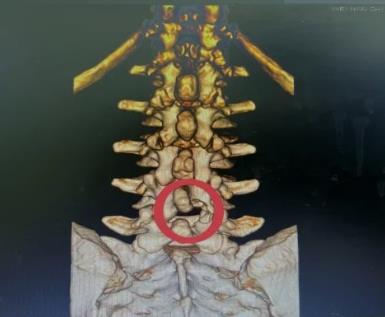

60岁的王某,女性,有3年“腰椎间盘突出伴椎管狭窄”病史。最近,她的腰痛加重,感觉到疼痛向双侧臀部放射,伴有双下肢沉重感。只能走大约300米就需要停下来休息,给她的日常生活带来很大困扰。王某来到市中心医院就诊,与骨科一病区医师详细交流,经仔细检查,发现患者病情比较严重,保守治疗效果不佳,而且狭窄部位比较深,采用普通的单轴椎间孔镜手术可能效果不好。经过骨一科医疗团队共同讨论,决定采用创伤小、恢复快、椎管减压更彻底的微创方案-UBE技术进行治疗。

做好充分准备后,程福宏主任、雷广宇副主任、张波副主任医师和张楠副主任医师等人共同合作,术中采用两个约1cm的切口,通过通道进行操作,对狭窄部位进行减压(ULBD),并摘除了突出的髓核。术后,患者明显感觉到双下肢松弛,可以自如行走,第二天手术后满意出院。